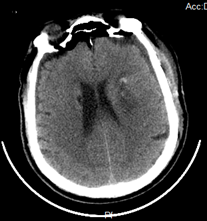

小骨窗开颅脑内血肿清除术

张xx,男,46岁

患者因“突发意识不清伴呕吐3小时余”入院

诊断:左侧基底节区脑出血,高血压病3级(极高危组)

入院:神志浅昏迷,GCS评分8分,双侧瞳孔圆形等大,直径2.5mm,对光反射迟钝,四肢肌力、肌张力查体不合作,右侧巴氏征阳性。

术前                           术后